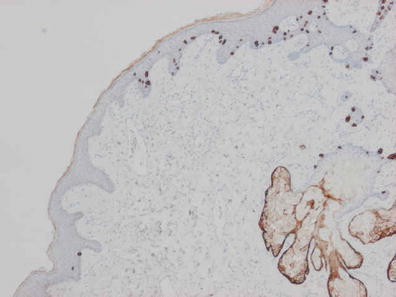

Objective: We report 10 cases of papillary carcinomas of the breast that histologically resemble PTC.

Method: These include 2 cases previously reported (Am. J. Surg. Pathol. 27, 1114–18, 2003) and 8 new cases.

Results: Patients were female of 54.7 years (mean age). All cases displayed neoplastic cells arranged in solid to papillary architectures and follicular structures resembling thyroid tissue. Cells evidenced eosinophilic granular cytoplasm and nuclei with clear chromatin with numerous grooves and occasional eosinophilic pseudoinclusions. All cases stained for mitochondria in >50 % of neoplastic elements. ER, PR, AR, Her-2, TTF1, Thyroglobulin were negative. Myoepithelial cells were absent in 8 cases. Cases were discovered mammographically, except for case 3 that had a lump present for 10 years. Sentinel nodes in 6 cases were negative. Case 3 had an intramammary metastatic lymph node. All patients are alive and well. No fewer than 3 had 10 year-FU.

Conclusion: Breast tumours resembling PTC have to be recognized to avoid misdiagnosis as metastatic PTC; they are triple negative tumours with indolent behaviour; the term tumour for these neoplasms seems appropriate as it is difficult, especially without immunohistochemistry, to establish their invasion.